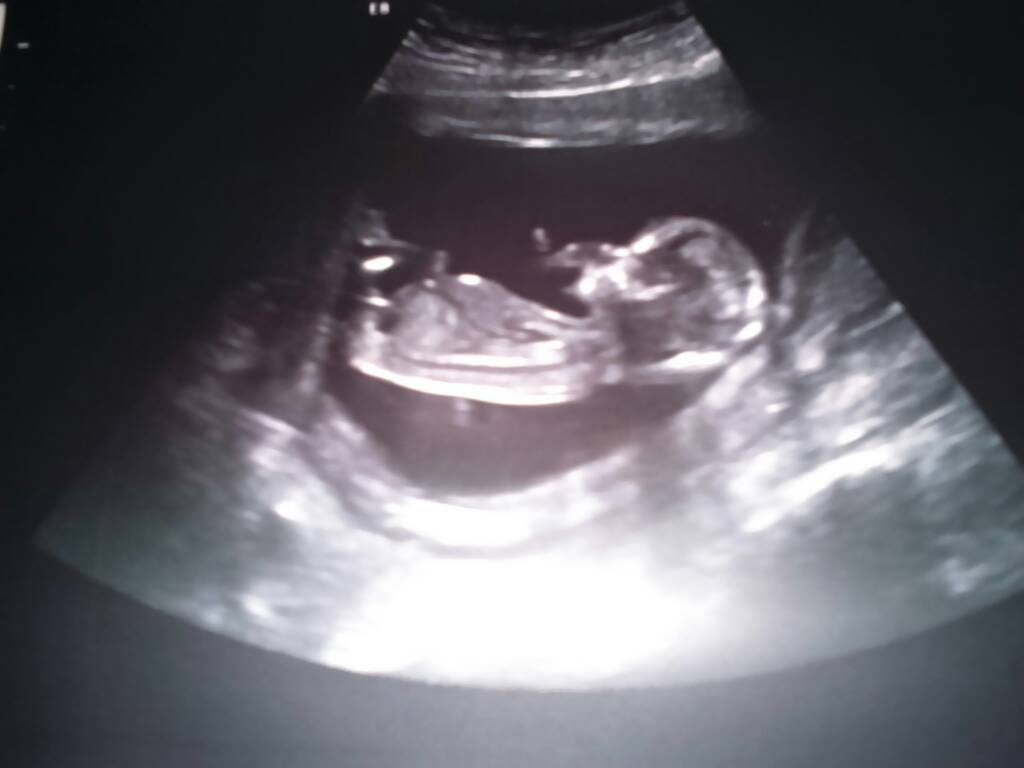

My też po wizycie!! Jestem prze szczęśliwa ! Wszystko w jak najlepszym porządku, wszyskie pomiary dobre, ma aż 75 mm

idealnie z miesiączką idzie

no i siusiak prawdopodobnie !

Marzyłam o dziewczynce, ale jak zobaczyłam te nóżki i rączki to takie obojętne mi się to zrobiło

na poczatku leżał sobie noga na nogę , a później machał nóżkami

lekarz pochwalił, że taki grzeczny hehe